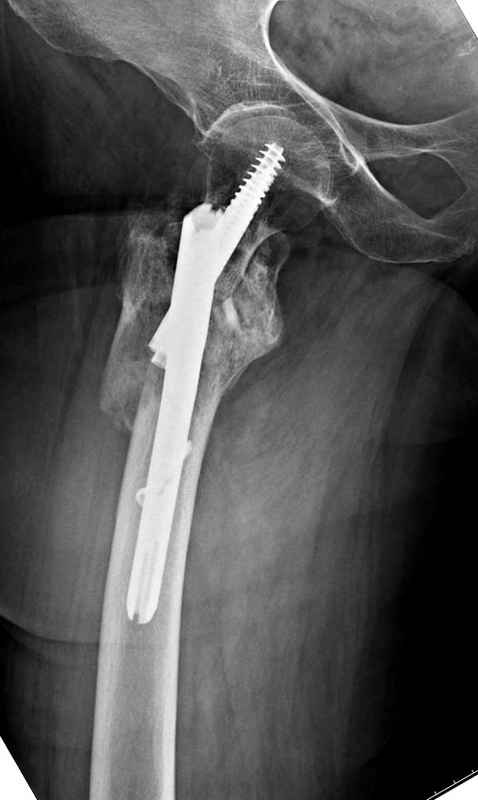

Из фиксаторов, мы бы применили цефаломедуллярные, потому что они "по закону моментов" из-за короткого рычага от центра головки к диафизу и по принципу "головка диафиз" механически лучше выдерживают нагрузки, чем пластины.

Здесь пара случаев фиксации похожих переломов:

первый высокоэнергетическая травма 36 лет